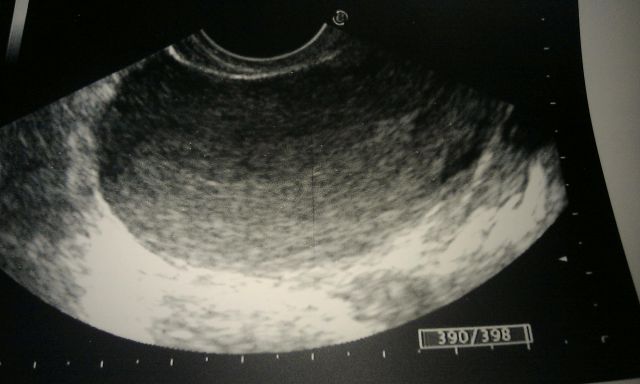

- Ультразвуковое исследование, на котором визуализируются толщина и структура эндометрия;

Часто исследования нужно проводить в определенные дни цикла или несколько раз на протяжении цикла. Это делается для того, чтобы отследить динамику изменения слизистой на протяжении цикла под действием гормонов.